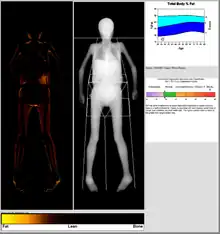

Body composition measurement

DXA scans can also be used to measure total body composition and fat content with a high degree of accuracy comparable to hydrostatic weighing with a few important caveats.[18] From the DXA scans, a low resolution "fat shadow" image can also be generated, which gives an overall impression of fat distribution throughout the body[19] It has been suggested that, while very accurately measuring minerals and lean soft tissue (LST), DXA may provide skewed results due to its method of indirectly calculating fat mass by subtracting it from the LST and/or body cell mass (BCM) that DXA actually measures.[20]

DXA scans have been suggested as useful tools to diagnose conditions with an abnormal fat distribution, such as familial partial lipodystrophy.[21][22][19] They are also used to assess adiposity in children, especially to conduct clinical research.[23]